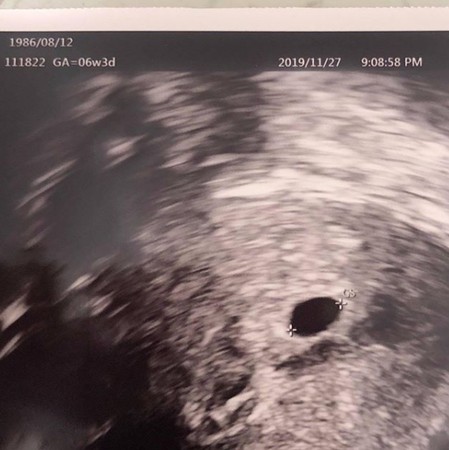

台湾歌手谢和弦混血妻Keanna亲自举报他吸毒,事发后整整1天以来保持沉默,不回应任何讯息,令粉丝十分担心。未料,事隔一日,她于6日晚间突然更新IG,发文贴出一张胎儿6周的超音波照,疑似宣布怀孕,令粉丝又惊又喜大呼“恭喜”、“辛苦了,加油”。

根据台湾媒体的报导,从“扣嫂”Keanna上传的超音波照中,可以看到是2019年11月27日拍下,至今应该已是怀孕8周。

虽然没有多做说明,但超音波照上标示“1986/08/12”,正是Keanna的生日,令网友猜想应该就是她本人的超音波照。于5日晚间,Keanna 亲自打电话报案,检举谢和弦吸毒,在警方上门问“这里有人在吸毒吗”的时候,哭着开门:“对的,请进来。”之后更看着谢和弦被带进派出所,而在后头伤心痛哭。